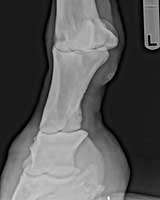

Colleen Cornett and EasyAn update on my horse Easy. GOOD NEWS... I just started him on my last refill bag and I am sure I will not need any more Ringbone Formula. He has not limped for at least 7 weeks now on maintenance dosage of 4 scoops a day. We have been riding him barefoot again for at least 2 months and have tested him out in the hills nearby. (His limping first showed up whenever he was going down a hill.) His ringbone was confirmed by x-rays by our local Vet. It has now been a little over 5 months and I am now tempted to take him back for some "after" x-rays but would rather spend the money on more of your formulas....